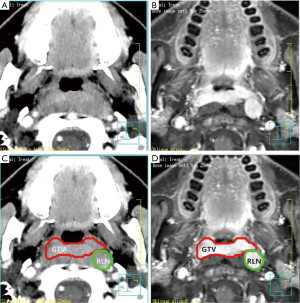

The primary tumor and the involved RLNs on each axial CT slice were both delineated on the planning system according to the pretreatment contrast axial T1-weighted MRI and CT fused images. In this study, the volume of RLNs was separated from primary nasopharynx tumor (Figure 1). For patients given induction chemotherapy, the targets of primary tumor volume were contoured based on the pretreatment MRI images. The inverse IMRT planning system developed by Philips (Madison, WI, USA), the Pinnacle version 8.0 planning system was used to do all treatment plans. The GTVnx, volume of RLNs (in cubic centimeters) was calculated subsequently by the same software. The primary gross tumor volume (GTVp) was obtained by summing the GTVnx and volume of RLNs.